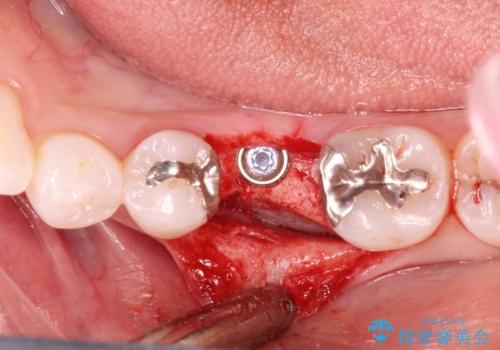

- 治療計画

- 保存不可能な歯の抜歯後、待時にてインプラントを埋入、2回法にて咬合回復を計画した。

同時に、前後の歯の金属のやり直しも行った。

インプラントの種類:strauman SLActive